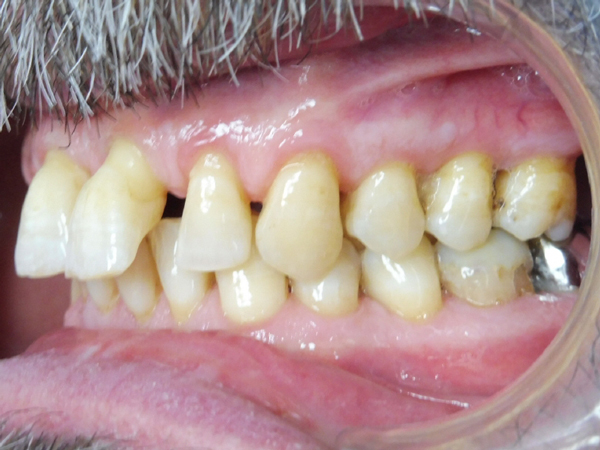

Arcade mandibulaire avant traitement orthodontique, séquelles de maladie parodontale

Arcade maxillaire avant traitement orthodontique, séquelles de maladie parodontale